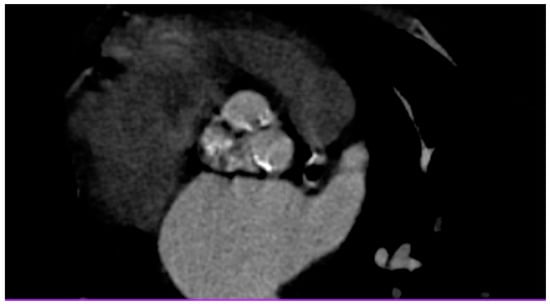

Cardiac Post-Chest Radiotherapy Complications in a 50-Year-Old Patient with Hodgkin Lymphoma

2. Case Report